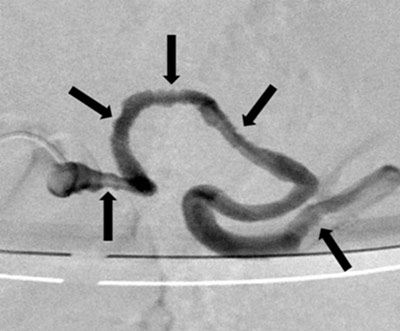

Figure 1

Abdominal aortic angiogram: the 2.5 cm large aneurysm of the distal splenic artery (arrows).

A 61-year-old male was admitted to our hospital for unconsciousness followed by melena. On admission, he remained hemodynamically stable with a hemoglobin level at 12 g/dl (normal values: 14–18 g/dl). The patient underwent an upper endoscopy which revealed a stomach full of fresh blood. Neither esophageal varices nor ulcer were found. The patient rapidly progressed to hemodynamic instability, requiring intubation and polytransfusion. He was then taken to the angiography suite. The global aortic angiogram demonstrated the existence of a saccular aneurysm of 2.5 cm in diameter on the distal third of a splenic artery which also showed irregular contours (Figure 1). This irregularity was not associated with the usual findings of spasticity (Figure 2a). However, it prevented the distal selective catheterization of the artery, using a 3F microcatheter. Given the impossibility of a “sandwich” coiling, we opted for a postostial embolization with microcoils, enabling hemodynamic stabilization (Figure 2b).